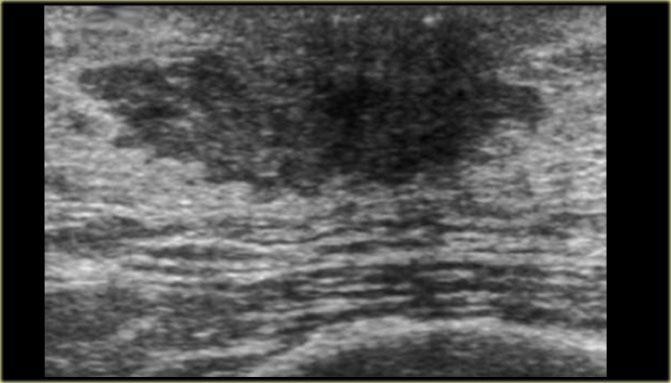

Bên trái là cùng hình siêu âm đó, nhưng ở tư thế bình thường.

Lưu ý hình ảnh trông ‘ác tính’ như thế nào.

Siêu âm cho thấy hình ảnh có gai.

Các trường hợp này minh họa rõ ràng rằng gynecomastia có thể có hình ảnh mà chúng ta sẽ gọi là ác tính ở phụ nữ.

Đáng tiếc là một số tổn thương ác tính ở nam giới lại có thể trông lành tính và chúng tôi sẽ trình bày một số ví dụ trong chương tiếp theo.